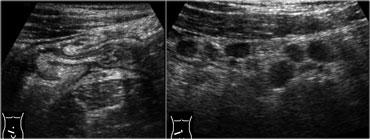

Viêm hồi manh tràng nhiễm khuẩn ở bệnh nhân có triệu chứng lâm sàng của viêm ruột thừa. Có hình ảnh dày thành lớp niêm mạc và dưới niêm mạc rõ rệt của hồi tràng và manh tràng.

Hình bên trái là một phụ nữ 26 tuổi với các triệu chứng lâm sàng của viêm ruột thừa.

Siêu âm cho thấy van hồi manh tràng nổi bật và dày thành lớp niêm mạc và dưới niêm mạc rõ rệt của hồi tràng và manh tràng.

Các hạch bạch huyết phì đại được phát hiện tại gốc mạc treo ruột.

Ruột thừa bình thường.

Phẫu thuật cắt ruột thừa đã được hủy bỏ.

Ngày hôm sau bệnh nhân xuất hiện tiêu chảy và kết quả cấy phân cuối cùng phát hiện Campylobacter jejuni.

Viêm hồi manh tràng nhiễm khuẩn. Siêu âm cho thấy dày thành lớp niêm mạc và dưới niêm mạc. Đại tràng lên co thắt với hình ảnh bờ múi nổi bật. Ruột thừa bình thường (mũi tên).

Trong viêm hồi manh tràng nhiễm khuẩn, siêu âm cho thấy các đặc điểm khá đặc trưng.

Có hình ảnh dày lan tỏa lớp niêm mạc và dưới niêm mạc của hồi tràng tận và manh tràng.

Ruột thừa phải bình thường trên siêu âm (Hình).

Trái ngược với bệnh Crohn hồi manh tràng, trong viêm hồi manh tràng nhiễm khuẩn, các lớp thành ruột luôn còn nguyên vẹn và lớp cơ cũng như thanh mạc không bao giờ bị tổn thương.

Ngoài ra, mạc nối lớn và mạc treo ruột không bao giờ bị ảnh hưởng và không bao giờ có dấu hiệu tắc ruột, hình thành áp-xe hay rò.